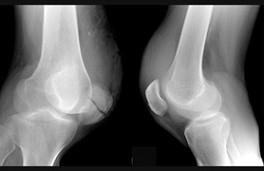

如图所示,髌骨横形骨折,造成的原因主要是 ( )A、积累劳损B、骨骼疾病C、直接暴力D、间接暴力E、肌肉拉力